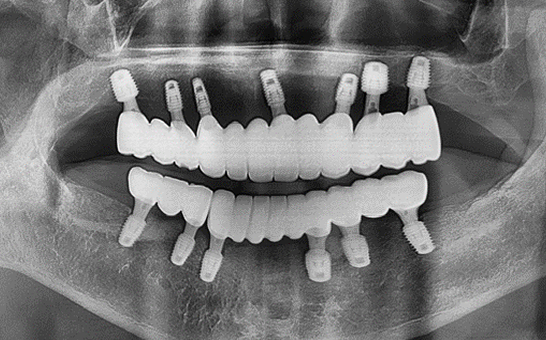

바른선택치과의원 전악 임플란트

before after

치료 시작 전 촬영 2024.01.24 | 치료 완료 후 촬영 2024.12.26

바른선택치과의원 실제 환자 전,후 사례

바른선택치과의원 임플란트 실제 사례

바른선택치과의원을 만나, 치아는 물론 삶까지 바뀌신 실제 환자분 전,후 사례를 확인하세요.